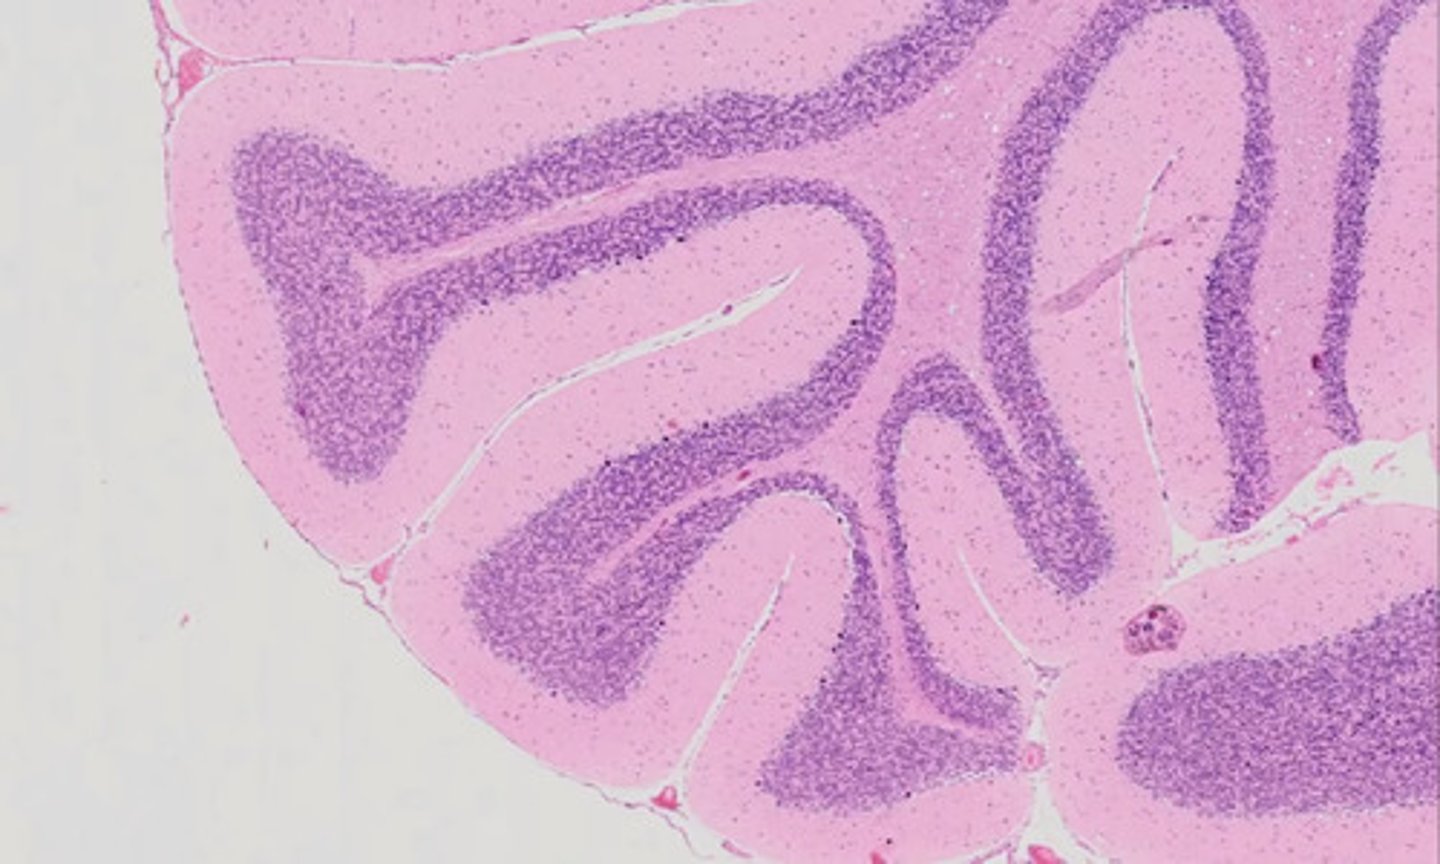

Móżdżek (H+E)